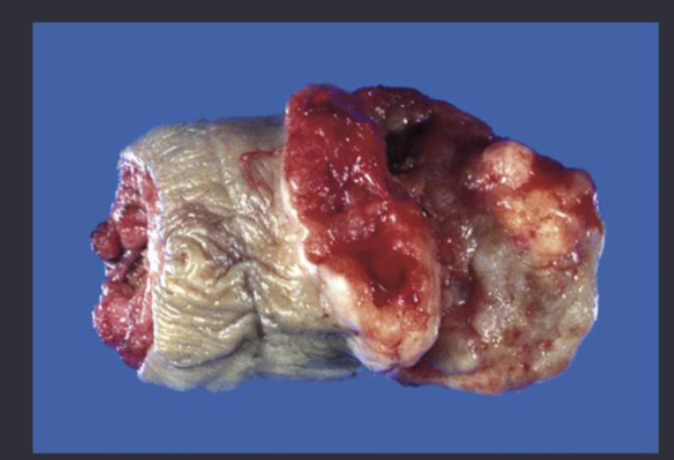

large discrete nodules on periurethral region leading to difficulty urinating are signs of…?

benign prostatic hyperplasia (BPH)

prostate cancer